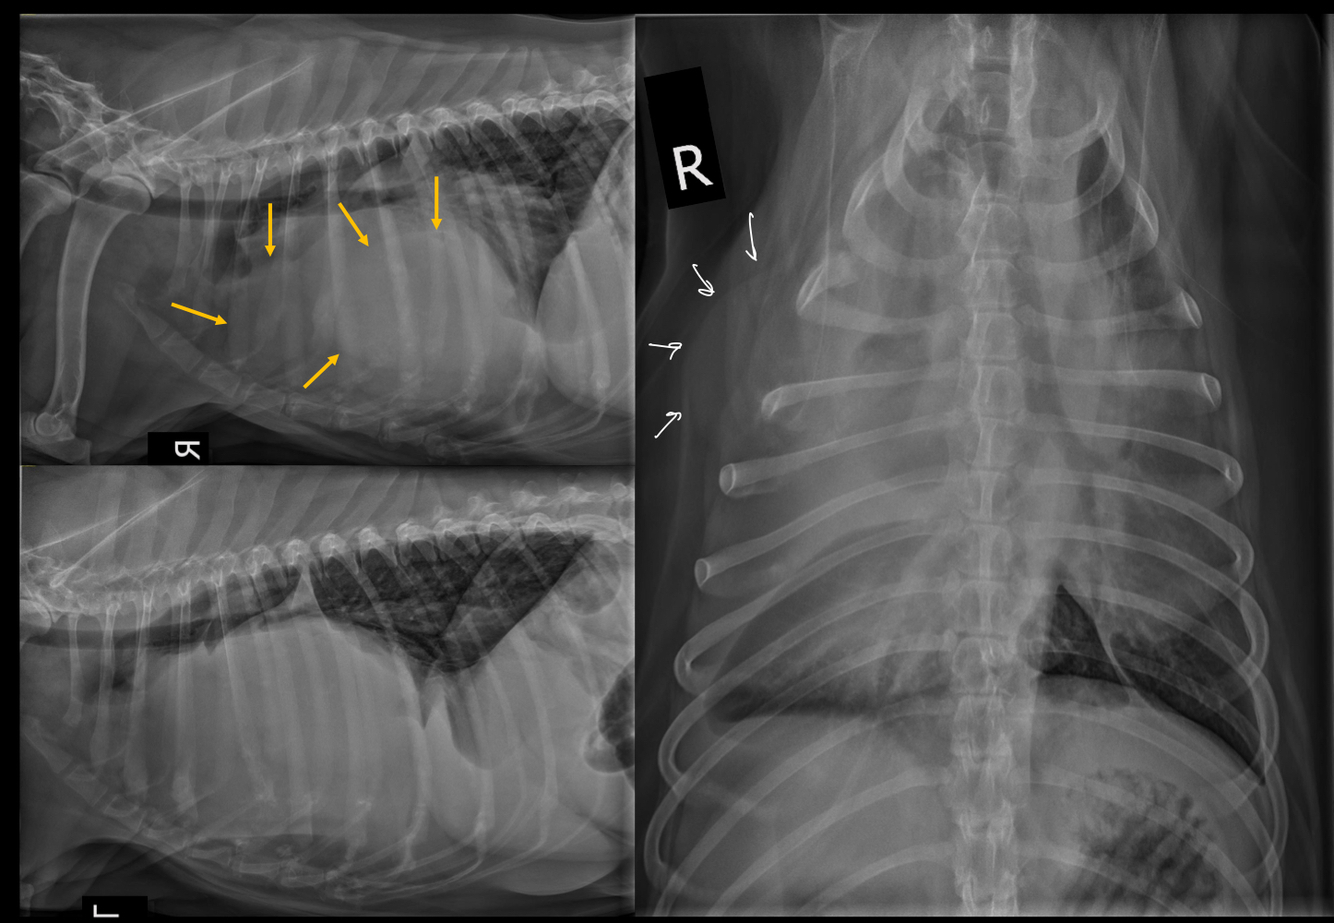

What is seen in these thoracic radiographs?

A

• sternal lysis and collapse with soft tissue swelling

• multiple, small pulmonary nodules

• osteolytic diaphysis and osteophyte formation